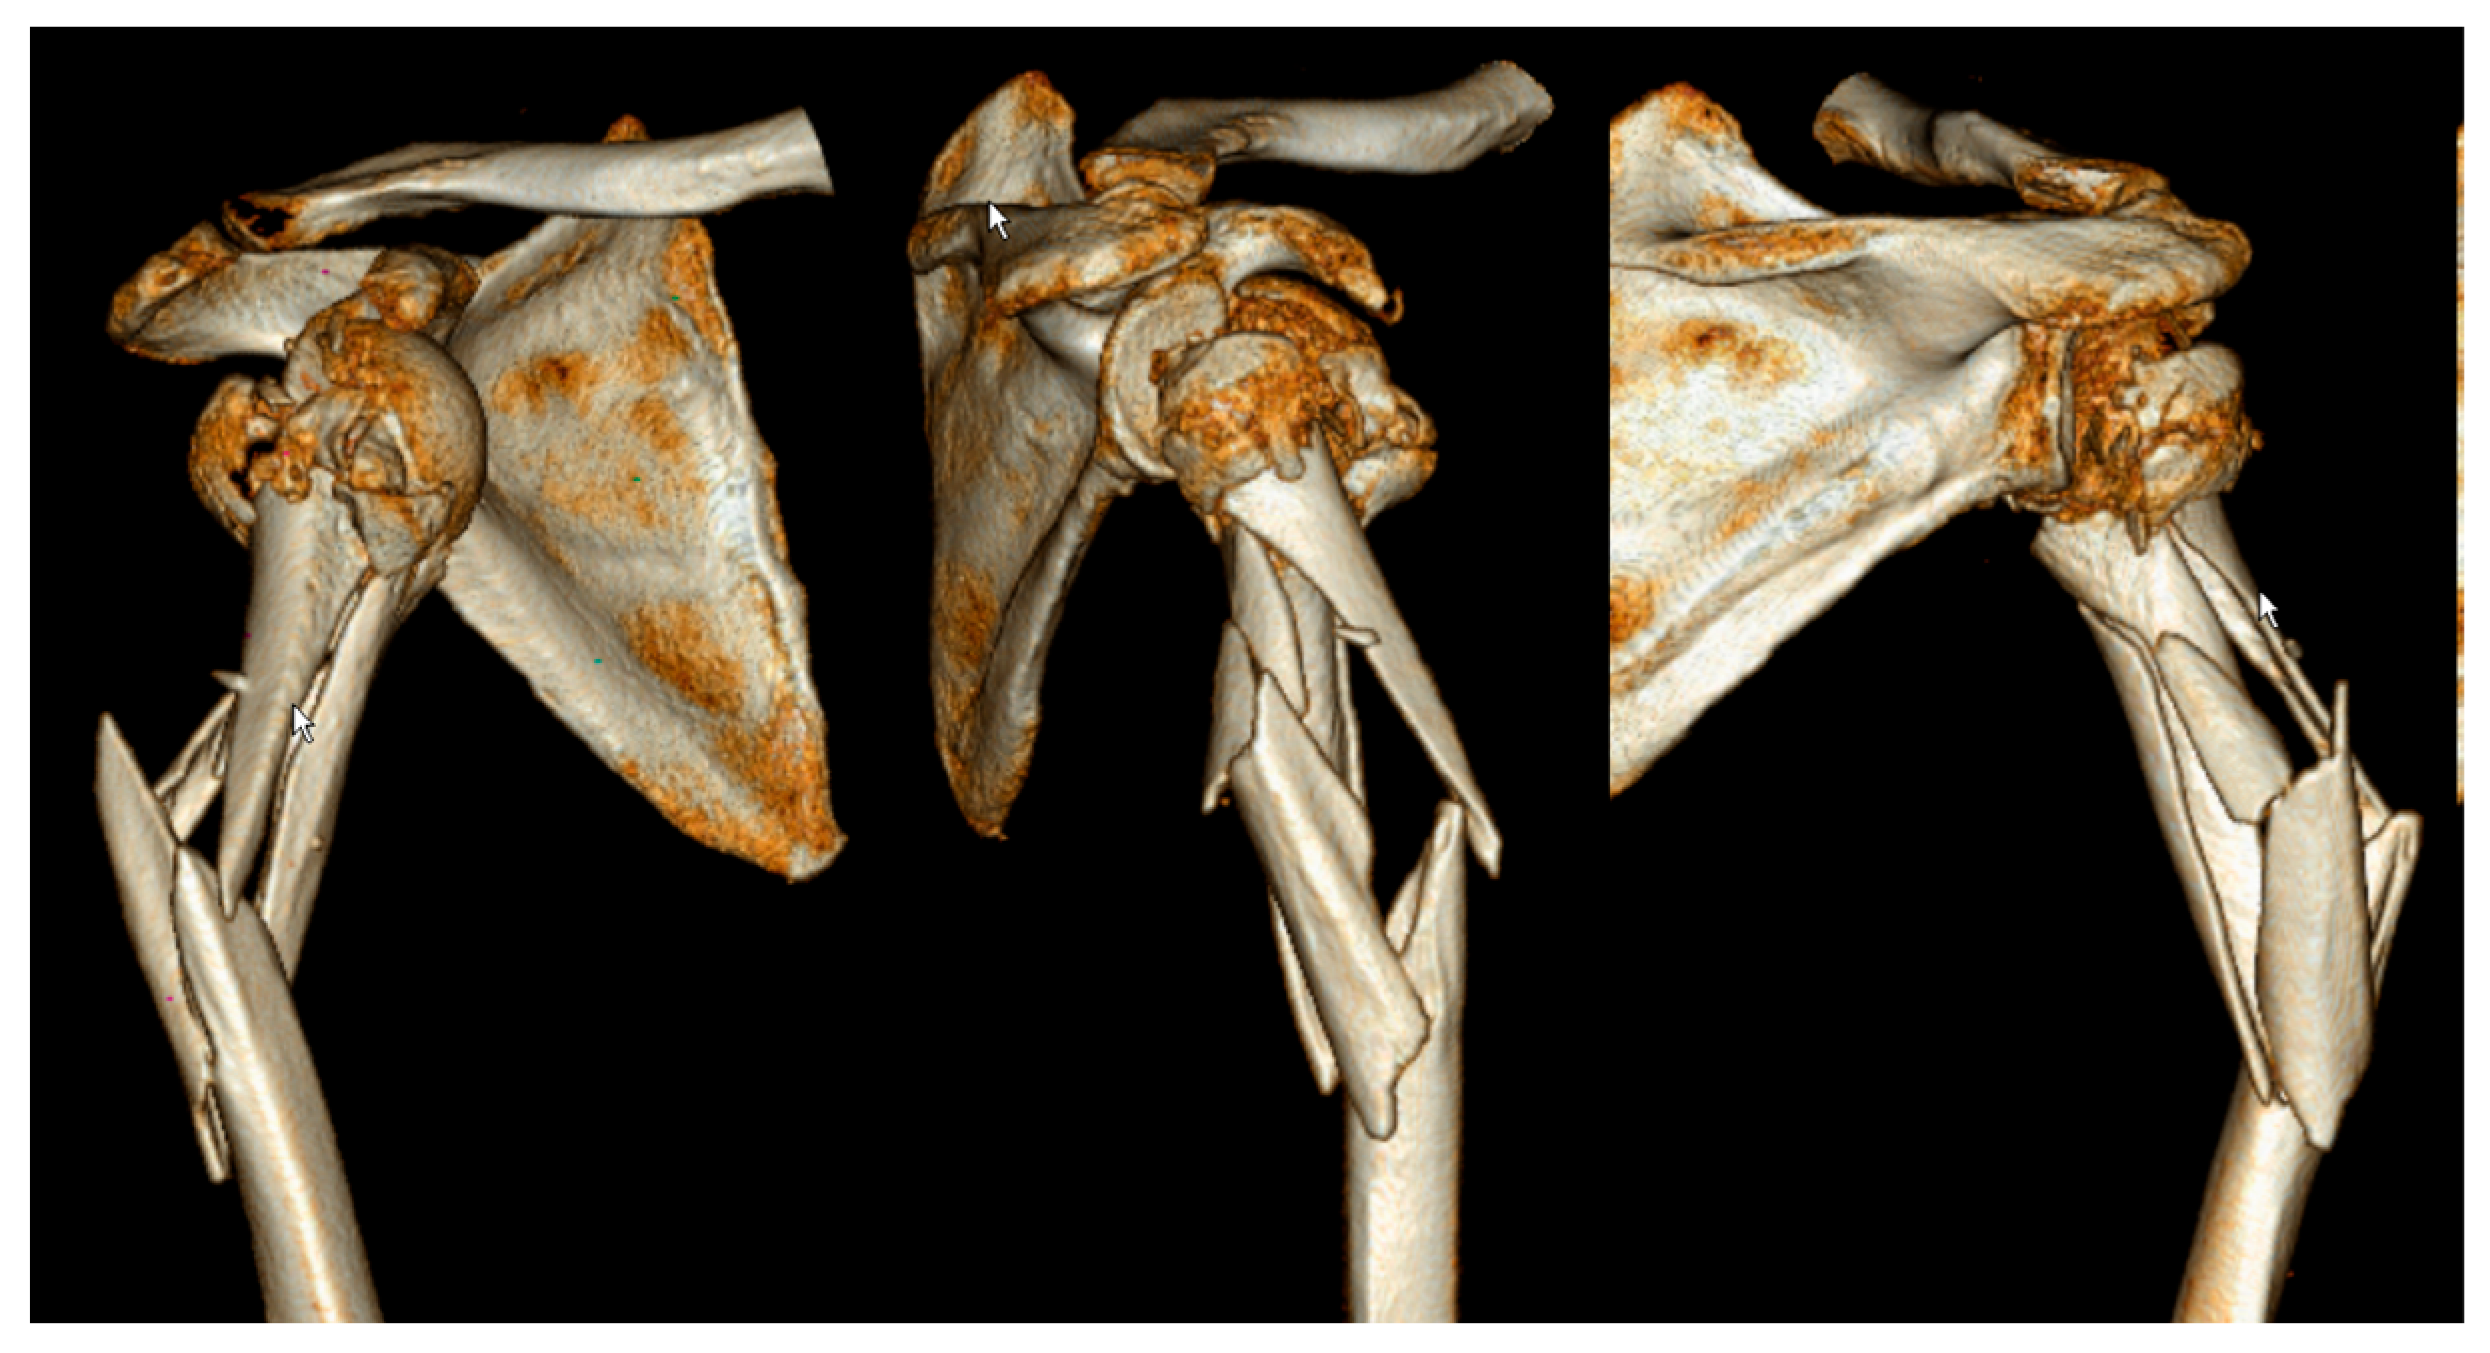

2. Materials and Methods

3. Results